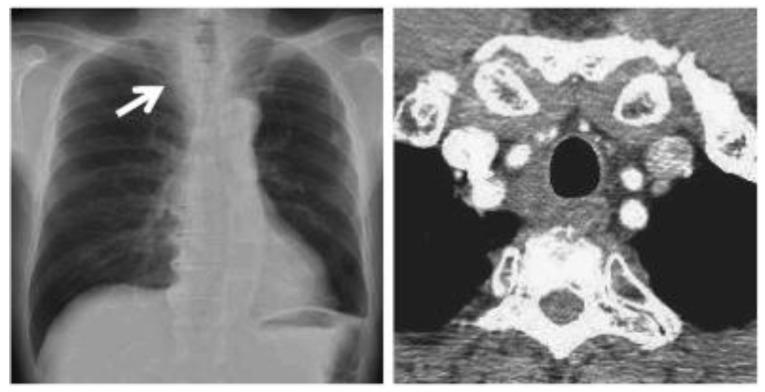

As less invasive options for surgical tumor removal, minimally invasive ablative techniques have gained popularity. Several solid tumors are being treated with cryoablation, a non-heat-based ablation technique. Cryoablation data in comparison over time demonstrates better tumor response and faster recovery. Combining cryosurgery with other cancer therapies has been explored to improve the cancer-killing process. Cryoablation with the combination of immunotherapy, results in a robust and efficient attack on the cancer cells. This article focuses on investigating the ability of cryosurgery to create a strong antitumor response when combined with immunologic agents resulting in a synergetic effect. To achieve this objective, we combined cryosurgery with immunotherapy using Nivolumab and lpilimumab. Five clinical cases of lymph node, lung cancer, bone, and lung metastasis were followed and analyzed. In this series of patients, percutaneous cryoablation and addressing immunity agents were technically feasible. In the follow-ups, there appeared to be no radiological evidence of new tumor development.

作为手术肿瘤切除的微创选择,微创消融技术已经越来越受欢迎。几种实体肿瘤正在接受冷冻消融治疗,这是一种非热消融技术。随着时间的推移,冷冻消融的数据显示出更好的肿瘤反应和更快的恢复。冷冻手术与其他癌症治疗方法的结合已被探索用于改善癌症杀伤过程。冷冻消融联合免疫疗法可以有效地攻击癌细胞。本文重点研究了冷冻手术与免疫药物联合使用时对肿瘤产生强烈抗肿瘤反应的能力,从而产生协同作用。为了实现这一目标,我们使用 Nivolumab 和 ipilimumab 将冷冻手术与免疫疗法相结合。对 5 例淋巴结、肺癌、骨和肺转移的临床病例进行了随访和分析。在这一系列患者中,经皮冷冻消融和免疫治疗具有技术可行性。在随访中,似乎没有新的肿瘤发展的放射学证据。